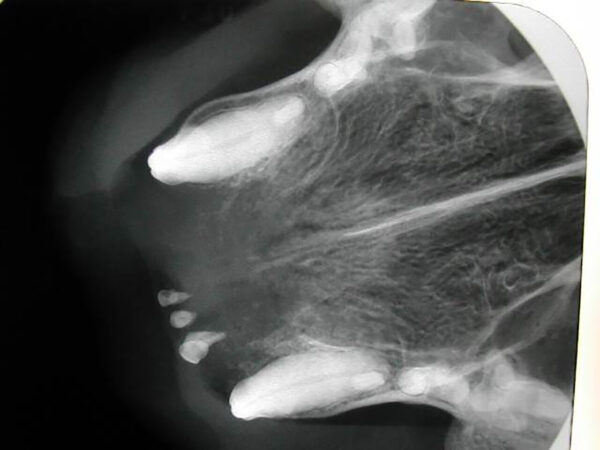

Alteración en el número y posición de los dientes

Ausencia dental

Cuando en una exploración visual de la boca observamos una ausencia dental debemos hacer una radiografía que nos indique la causa, que puede ser de origen genético o deberse a alteraciones sufridas durante las primeras etapas del desarrollo dental o a lo largo de la vida del animal.

A nivel radiológico nos podemos encontrar con varias situaciones:

- Ausencia del diente porque no se ha formado (agenesia).

- El diente no ha erupcionado por estar ectópico (fuera de su área anatómica).

- El diente está incluido o impactado (cuando no logra erupcionar o lo hace parcialmente por diferentes causas).

También puede ser debida a la pérdida dental (por EP, por ejemplo) o a fracturas de corona en las que quedan restos de estructuras dentales bajo la encía. Por tanto, dependiendo de ello, decidiremos el enfoque terapéutico que tomaremos en cada paciente con ausencia dental. (imágenes 14-17).

Aumento del número de dientes

La presencia de dientes supernumerarios también debe ser estudiada mediante la radiología intraoral. La causa principal es genética y la radiología nos permitirá valorar su naturaleza, si se trata de un diente definitivo o la falta de exfoliación de dientes deciduos (en caso de no tenerlo claro a la inspección visual). En este último caso, podremos valorar el estado de la raíz y su relación con el diente permanente, aspectos que debemos tener en cuenta a la hora de realizar su extracción (imágenes 18 y 19).

Las consecuencias pueden ser insignificantes en zonas de mínima intercuspidación, pero pueden ser causa de lesiones traumáticas o apiñamiento que disminuyan los mecanismos fisiológicos de autolimpieza.